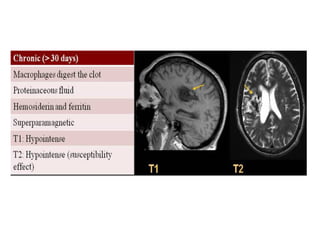

e) Chronic Infarct :

-In the chronic stage of infarction , cellular debris and

dead brain tissue are removed by macrophages and

replaced by cystic encephalomalacia and gliosis

-Infarct involvement of the corticospinal tract may

cause mass effect , mild hyperintensity on T2 and

eventual atrophy of the ipsilateral cerebral peduncle

& ventral pons due to Wallerian degeneration , these

changes can first be seen in the subacute phase with

atrophy being predominant feature in the chronic

stage (See later)

-DWI has usually returned to normal in the

chronic stages

-Occasionally , cortical laminar necrosis can

develop instead of encephalomalacia , cortical

laminar necrosis is a histologic finding

characterized by deposition of lipid-laden

macrophages after ischemia that manifests on

imaging as hyperintensity on both T1 & T2